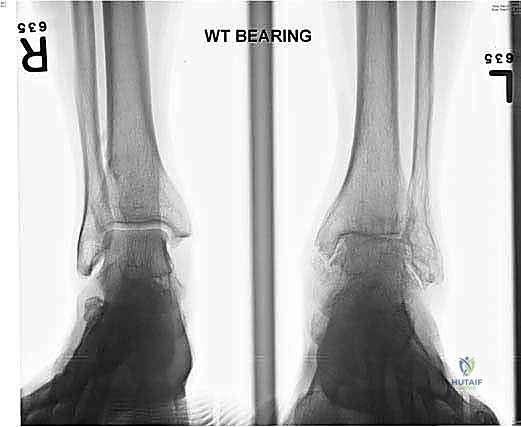

- الأشعة السينية الحاملة للوزن (Weight-Bearing X-rays): هي المعيار الذهبي المبدئي. تظهر تضيق المسافة المفصلية، تكون النتوءات العظمية (Osteophytes)، والتكيسات العظمية (Subchondral cysts).